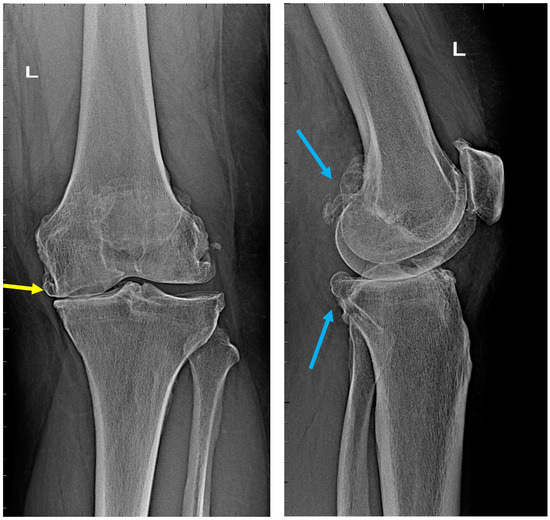

According to the classification of Kellgren, Lawrence, and Crofty-Lane, a classic X-ray examination, which is most often performed in anterior–posterior and lateral projections, defines the disease at the stage of advanced cartilage defects, which lead to secondary changes in the joint (Figure 2).

The patients underwent radiological assessment in accordance with generally accepted standards of radiological diagnostics. Based on the radiographs taken in the anterior–posterior and lateral positions, the severity of the osteoarthritis was determined on the Kellgren–Lawrence scales (Figure 3). On the first scale, patients were assigned to the appropriate degree of osteoarthritis, from grade 0 to 4.

Figure 2. Osteoarthritis of the left knee joint, stage 4 on the Kellgren–Lawrence scale. Advanced destruction of the medial condyle of the femur (upper part) and tibia (lower part). Roentgenograms in AP (left) and lateral positions (right). Source: proprietary material.

Figure 3. Radiographs of the knee joint. Grade-4 arthrosis on the K–L scale, grade 3 on the Crofty-Lane scale. Left—AP view, right—lateral view. Visible (yellow arrow) complete narrowing of the joint space in the medial compartment, numerous osteophytes (blue arrows), and joint-axis disorders. Upper part: femoral bone, lower part: tibia and fibula. Source: proprietary material.